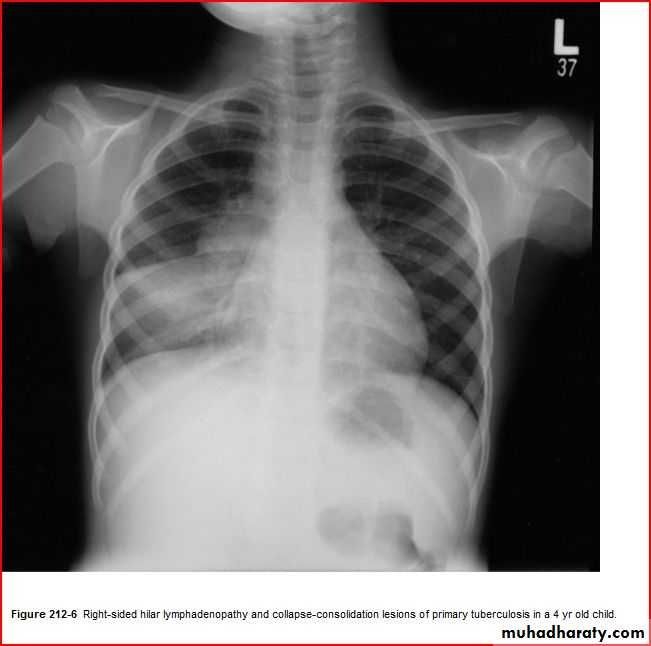

Enlarged hilar lymph nodes + non hemogenous opacity of middle and lower lobe

TBPleural effusion meniscal sign